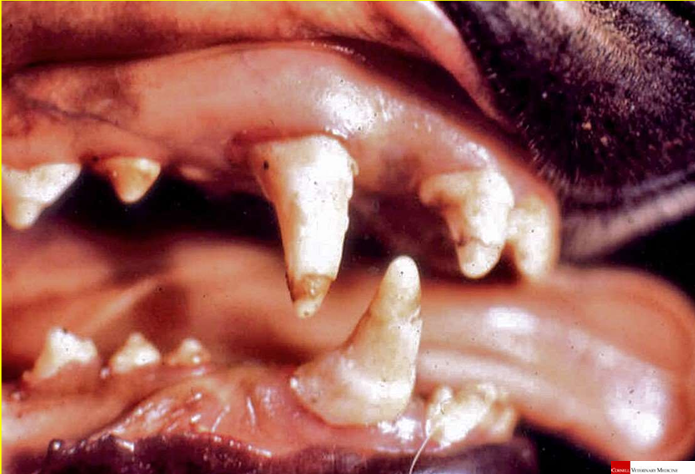

ENFERMEDAD PERIODONTAL

gingivitis y periodontitis con resorción ósea

se pueden perder dientes, pulpitis, osteomielitis

HIPERPLASIA GINGIVAL (braquicéfalos)

respuesta a la enfermedad periodontal